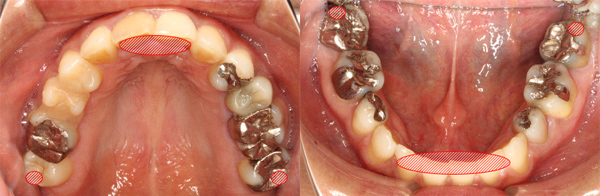

当院の審美治療ではセラミック治療も行っております。

セラミック治療とは白く透明度の高いセラミック製の人工歯を補う方法です。

近年、セラミックの技術が進化し、崩壊の進んだ口腔でも美しく、

見た目や機能も自分の歯と同じような耐久性のある修復治療が可能になってきました。

当院では下記のセラミック修復を行っております。

の中には、100%セラミック製のものから、金属を裏打ちしたメタルボンドセラミック、人工ダイヤモンドと呼ばれるジルコニアセラミックなどがあります。いずれも共通しているのが、セラミックの陶器の素材ならではの審美性の高さです。白く透明感のある天然の歯を好み、歯を補っていることを人に気づかれたくない方におすすめです。

また、セラミックは汚れが付着しにくいことや、セラミックの下の歯と密着しやすいことから、むし歯リスクを下げるメリットもあります。

また、セラミックには金属を使わないものもありますので、金属アレルギーの方にも適応できます。また、奥歯の場合は強度の高いジルコニアかメタルボンドがおすすめです。